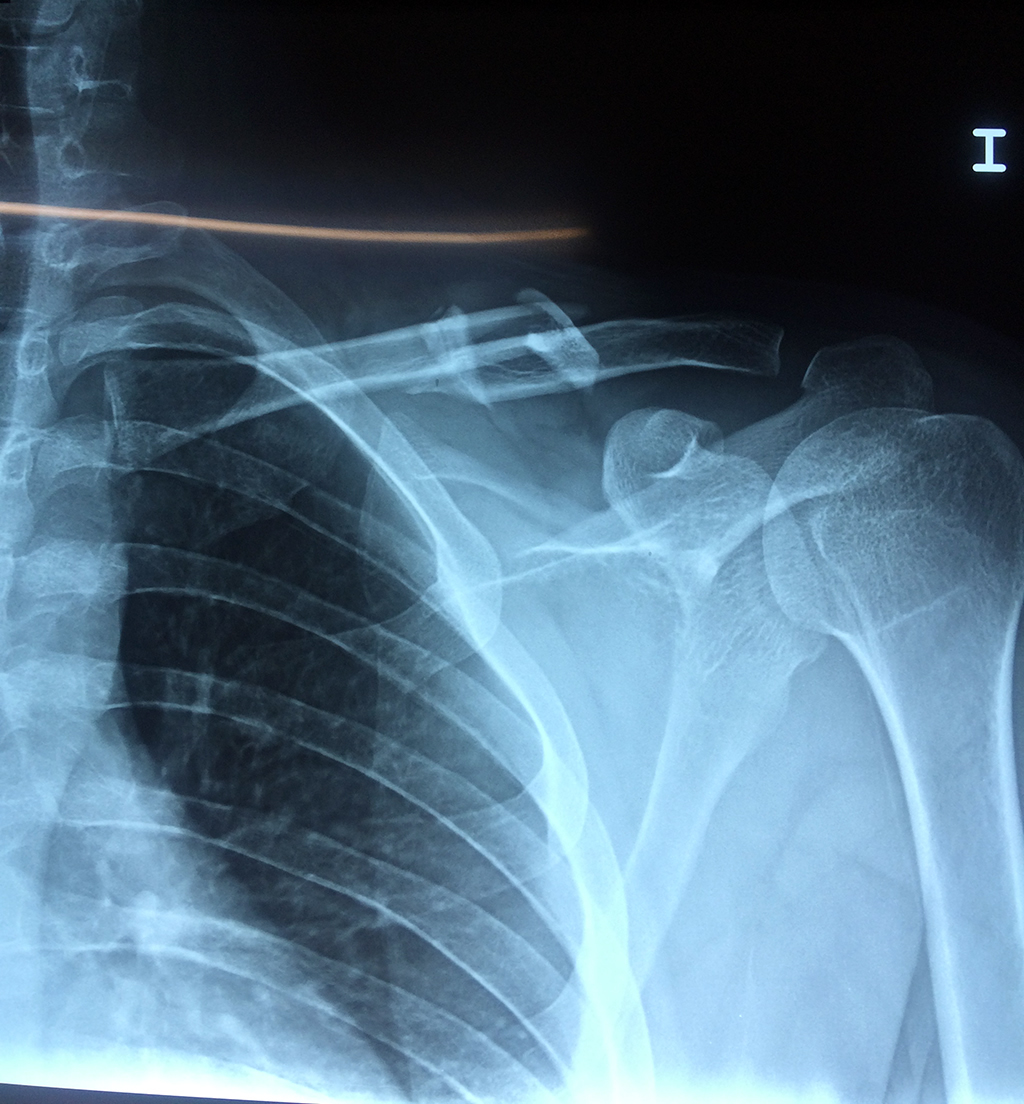

La clavícula es un hueso largo, con forma de "S" itálica, situado en la parte anterosuperior del tórax. Junto con la escápula forman la cintura escapular. Se puede palpar por toda su longitud y se extiende del esternón al acromion de la escápula, siguiendo una dirección oblicua lateral y posterior.